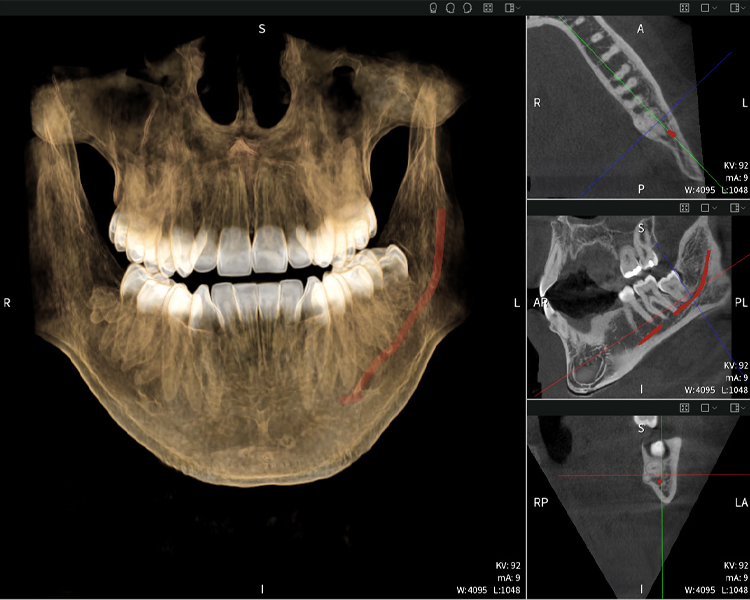

A continuación encontrarás un caso del Dr. med. dent. Oliver A. Centrella, en el cual las imágenes CBCT obtenidas con Seethrough Max proporcionaron información crucial sobre la anatomía compleja y la relación crítica entre las muelas del juicio y el nervio alveolar inferior. En este caso, existe una indicación para la extracción quirúrgica de las muelas del juicio.

Figura d: Resultados de imagen de Seethrough Max, sobre un fondo negro.

Las figuras b–d muestran varias vistas de una reconstrucción 3D de la mandíbula, proporcionando una visión general completa de la anatomía mandibular, la posición de los nervios en relación con los dientes y permitiendo evaluar la simetría y alineación dentaria.